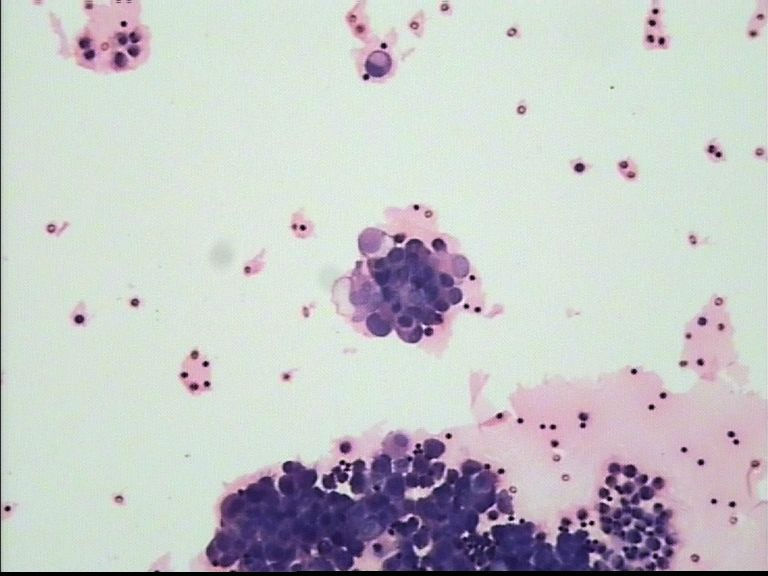

54岁 女 胸水

细胞学制片如何做才可以细胞退变的没有这么厉害?有哪位老师可以详细的讲解下吗?